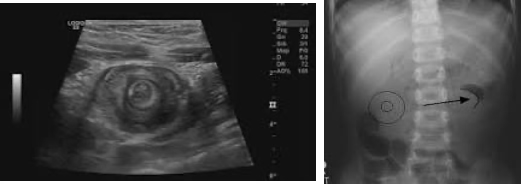

• 복부 초음파: 가장 유용한 진단 도구로, '과녁 모양(Target sign)' 또는 '도넛 모양(Doughnut sign)'이 특징적 소견

• 복부 엑스레이: crescent sign

• 공기 또는 바륨 관장: 진단과 동시에 치료 목적으로 시행될 수 있음. 장이 말려 들어간 부위가 '나선형 용수철(coil spring)' 모양으로 보이면서 filling defect 확인